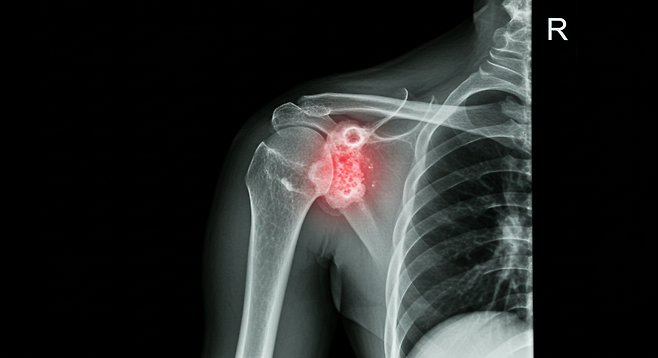

50대 이상은 칼슘만 먹으면 오히려 뼈가 약해진다?

정확한 뼈 건강 관리법과 주의해야 할 점